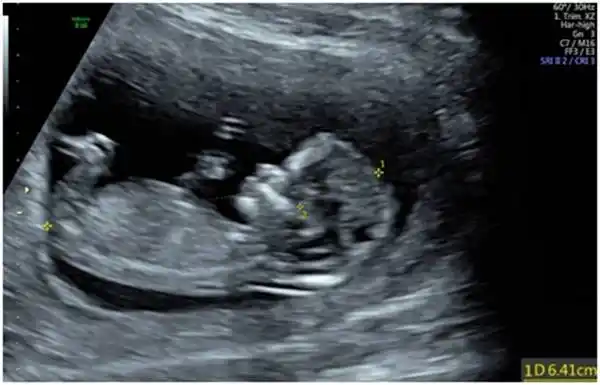

皮肤开始出现毛囊,肝脏开始活动头部占胎儿身长的一半外部生殖器官